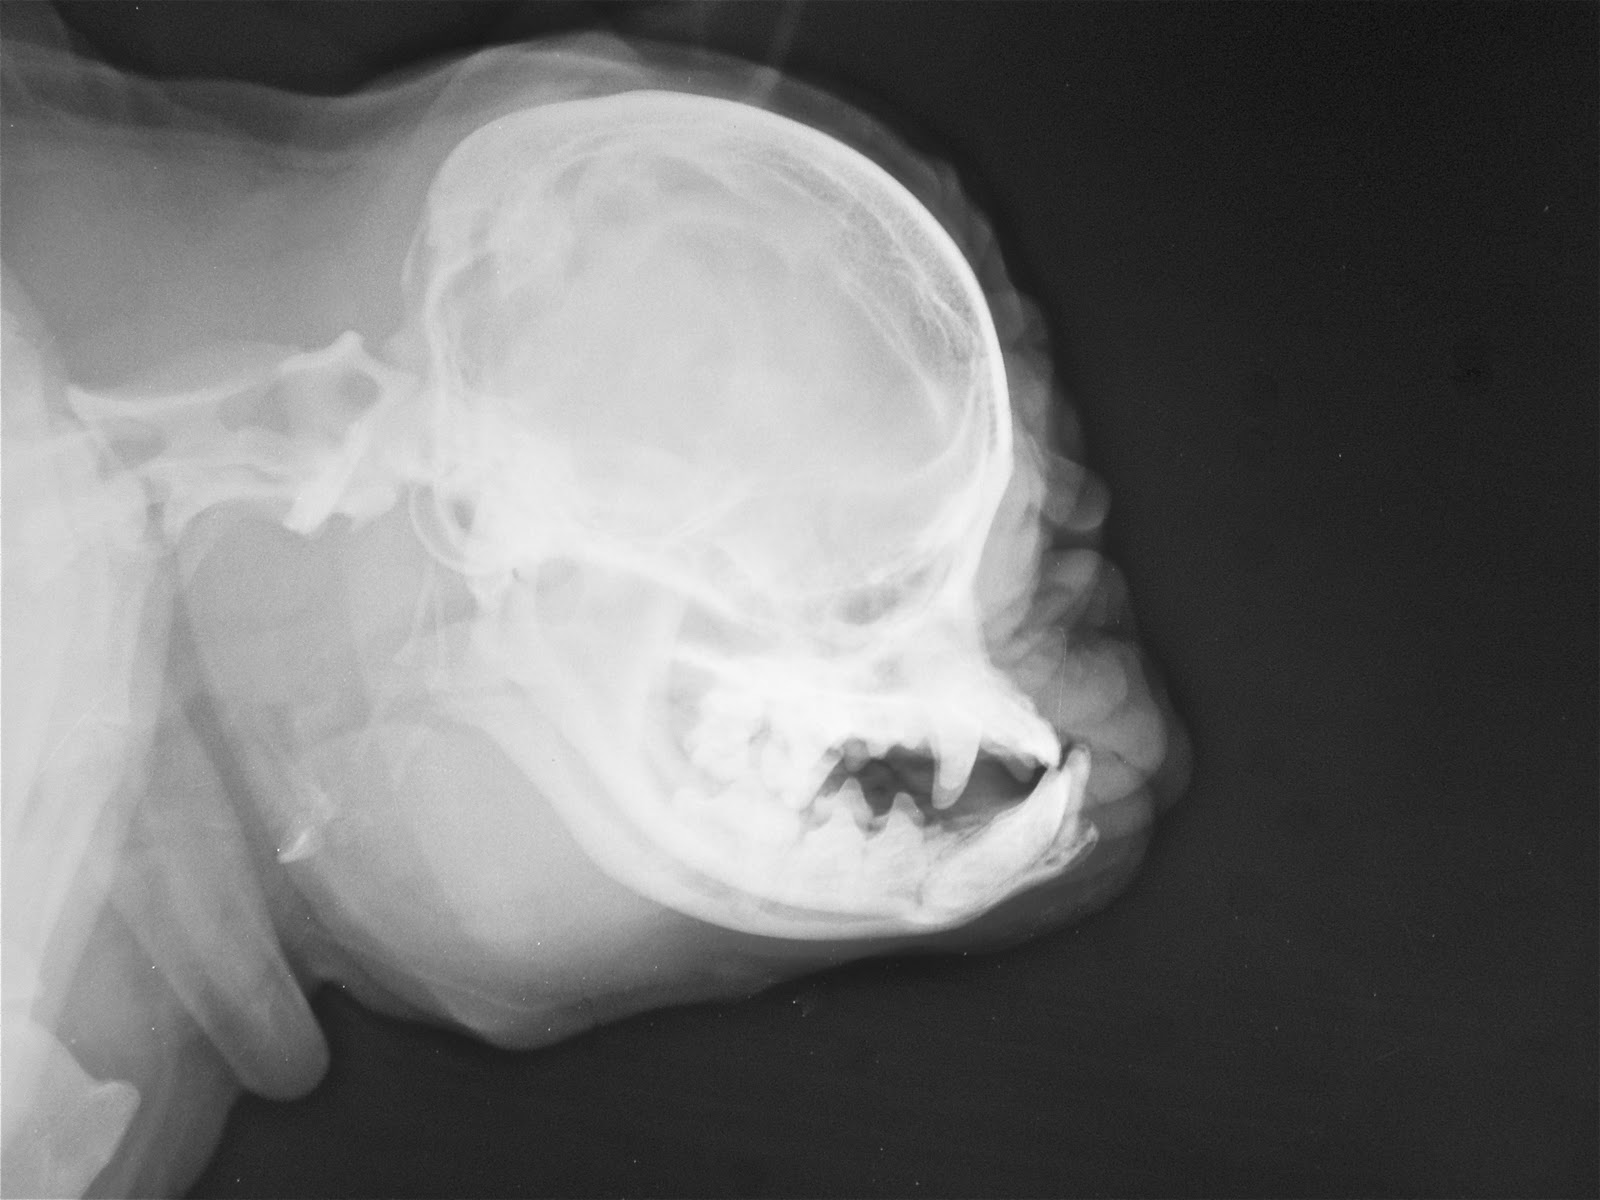

These Skull Of A Pug Images Show How Prone These Dogs Are To Health How To Clean Your Pug S Face In fact, why not treat it as a bonding time for you and your pug each. first, baba cleans my eyes to remove any dirt, then my forehead fold and chin and muzzle area. pugs need to have their faces washed and dried daily. one of the primary health risks for a pug is infections growing inside. How To Clean Your Pug S Face.